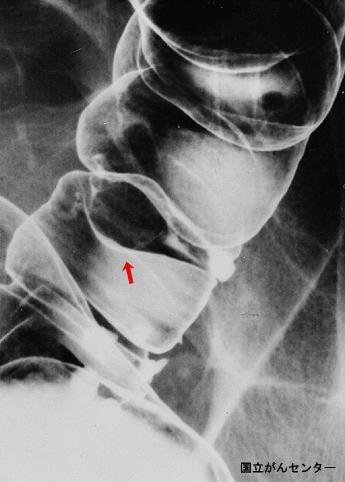

疾病(病理主体)的分类肿瘤样病变/大肠深部囊肿症

部位(按器官分)大肠/降结肠

检查方法X线

肿瘤的肉眼分类0型(表在型)/I型(Is)

肿瘤最大直径15~19

肿瘤的深度sm